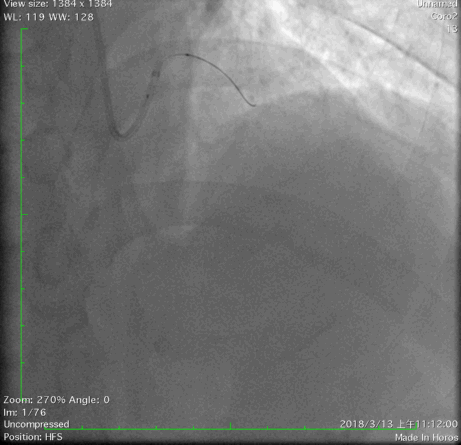

经右股动脉(8F),送EBU 3. 5指引导管指引导管至左冠开口。Sionblue导丝至LCX保护,Finecross 130到达LCX远端待命。Sionblue引导Corsair 135cm微导管进入LAD。近段纤维帽坚硬(伴钙化随后IVUS证实)尝试使用Gaia1st进入前次假腔,导丝升级Gaia 3rd谨慎前进入间隔支S1,推送corsair进入S1交换KDLC,Pilot 200导丝平行进入LAD真腔。Corsair交换Sionblue到LAD远端。IVUS证实全程真腔,闭塞段以纤维为主。植入支架完成血运重建。

G3前进

Pilot扭身进入lad

Pilot200进入真腔